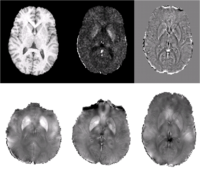

Quantifying magnetic susceptibility in the brain from the phase of the MR signal provides a non-invasive means for measuring the accumulation of iron believed to occur with aging and neurodegenerative disease. Phase observations from local susceptibility distributions, however, are corrupted by external biasfields, which may be identical to the sources of interest. Furthermore, limited observations of the phase makes the inversion ill-posed. We describe a variational approach to susceptibility estimation that incorporates a tissue-air atlas to resolve ambiguity in the forward model, while eliminating additional biasfields through application of the Laplacian. Results show qualitative improvement over two methods commonly used to infer underlying susceptibility values, and quantitative susceptibility estimates show better correlation with postmortem iron concentrations than competing methods.

We present a variational approach for Atlas-based Susceptibility Mapping

(ASM) that performs simultaneous susceptibility estimation and biasfield

removal using the Laplacian operator and a tissue-air susceptibility atlas. In [7,

8, 6] it was shown that applying the Laplacian to the observed field eliminates

non-local biasfields due to mis-set shims and remote susceptibility

distributions (ie. the neck/chest).

In this method, large deviations from the susceptibility atlas are penalized,

discouraging the estimation of artifactual susceptibility eigenfunctions in regions near

tissue-air boundaries where the Laplacian may not be sufficient to eliminate the

contribution of non-local sources and substantial signal loss corrupts the observed field.

Agreement of predicted and observed fields

within the brain is also enforced, but deviations in estimated susceptibility values outside the

brain are not penalized, allowing values at the boundary to vary from

the atlas-based prior to account for unmodeled external field sources (ie. shims).